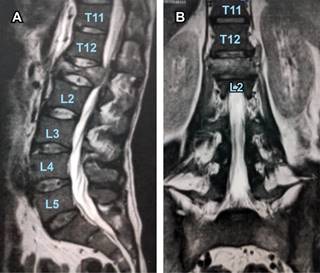

Figura 2: Resonancia magnética en cortes sagital (A) y coronal (B) que muestran una fractura por compresión secundaria a destrucción vertebral por metástasis de carcinoma epidermoide.